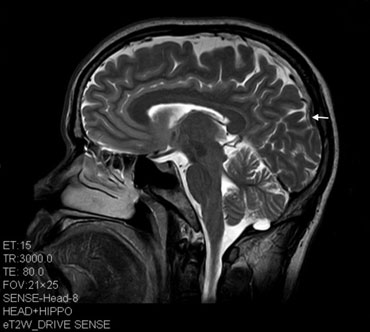

MRI scans of people who have abused ketamine for a long time reveal brain damage (though other factors could be sources of that damage). And studies on animals show ketamine-induced brain damage, too. But not much is known about esketamine’s long-term effects in people taking it for severe depression. “If you take ketamine for too long — and it’s unclear what too long is — that’s going to be a problem,” Iosifescu says. “Nobody can really tell you where this boundary is.”